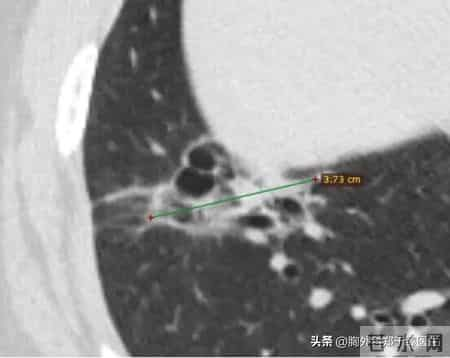

这是一名53岁的女性,于2023年10月做CT检查时发现了一个右下肺的结节,考虑肺癌。

CT显示为一个紧贴胸膜的右下肺囊腔型病灶,最大径3.7 cm,符合肺癌表现。